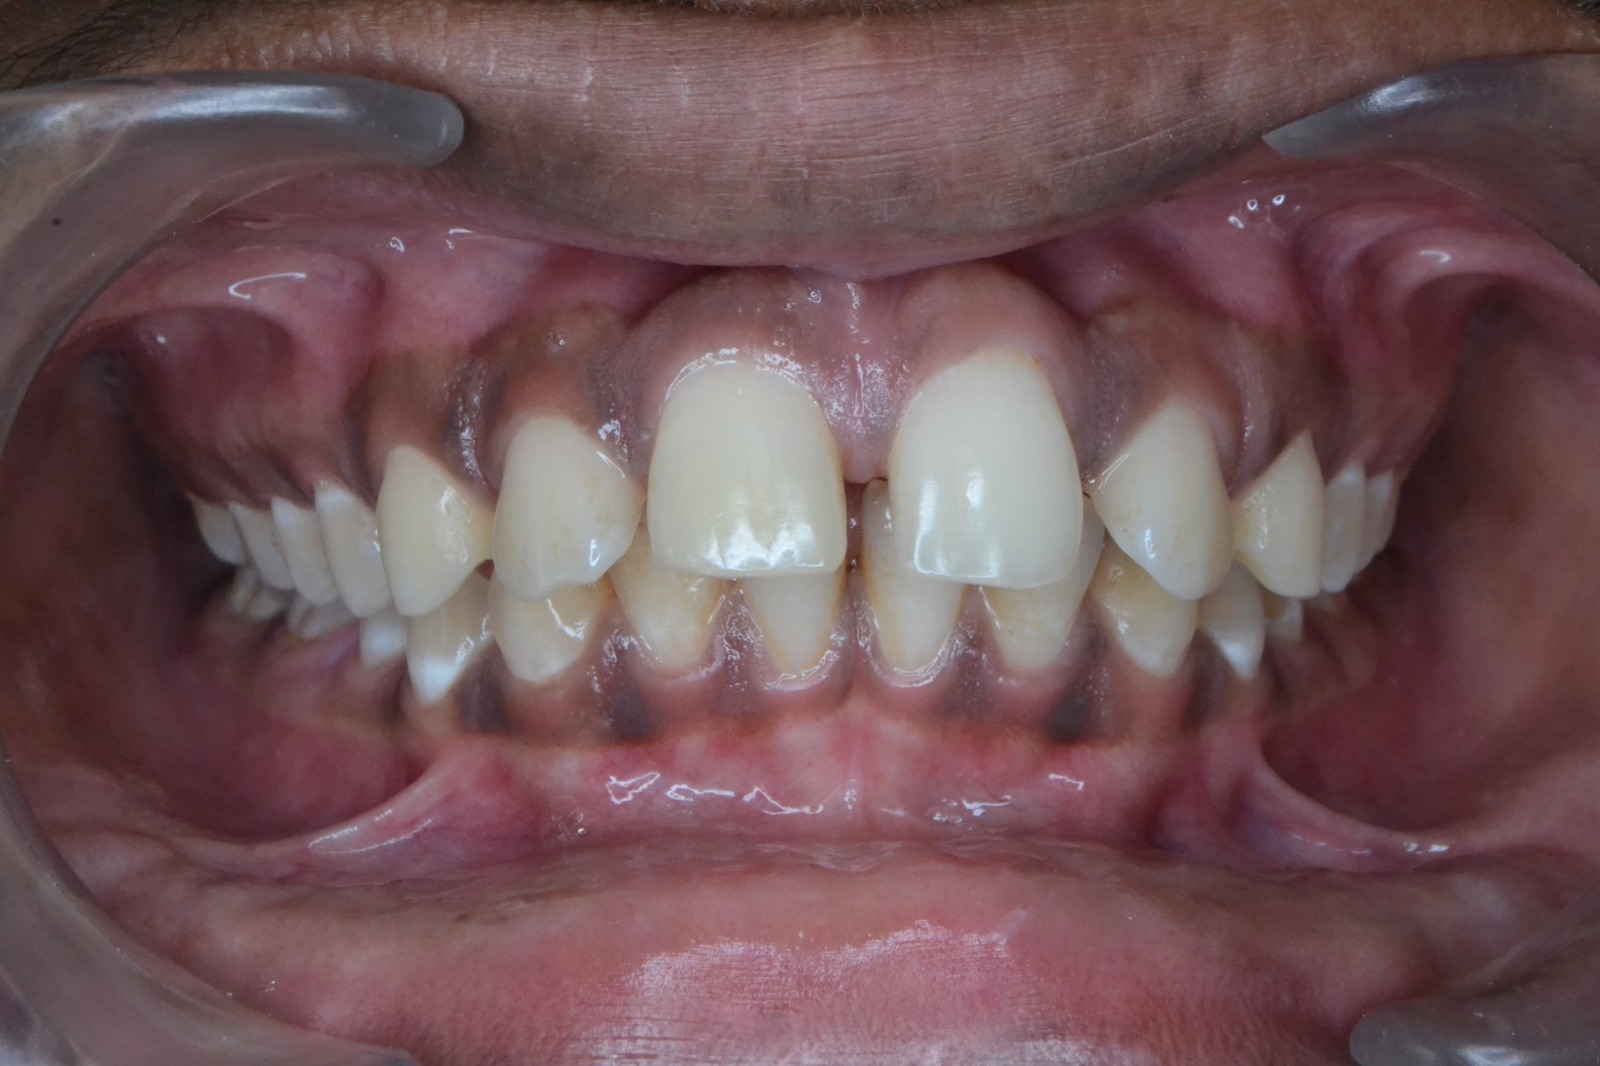

Sairam dental care located in Dharmapuri, with Leading Dentist In Oddapatti, is the Dental Hospital with exclusive root canal, Braces & Invisalign center. Led by renowned Drs Raghuraaman ( Periodontist) and Nivetha Raghuraaman ( Orthodontist) Sairam dental care offers gum treatment with expertise in laser, root canal treatment and digital smile correction with advanced technology aim to focus on aesthetics, comfort and precision. The clinic also specializes in Invisalign treatment, digital smile makeover, laser gum care, dental implants, root canal therapy, extractions and full-mouth rehabilitation blending compassionate care and clinical excellence.

Our professional, experienced, and passionate dentists make us the best choice for Invisalign treatment in Dharmapuri, providing top-notch dental services.